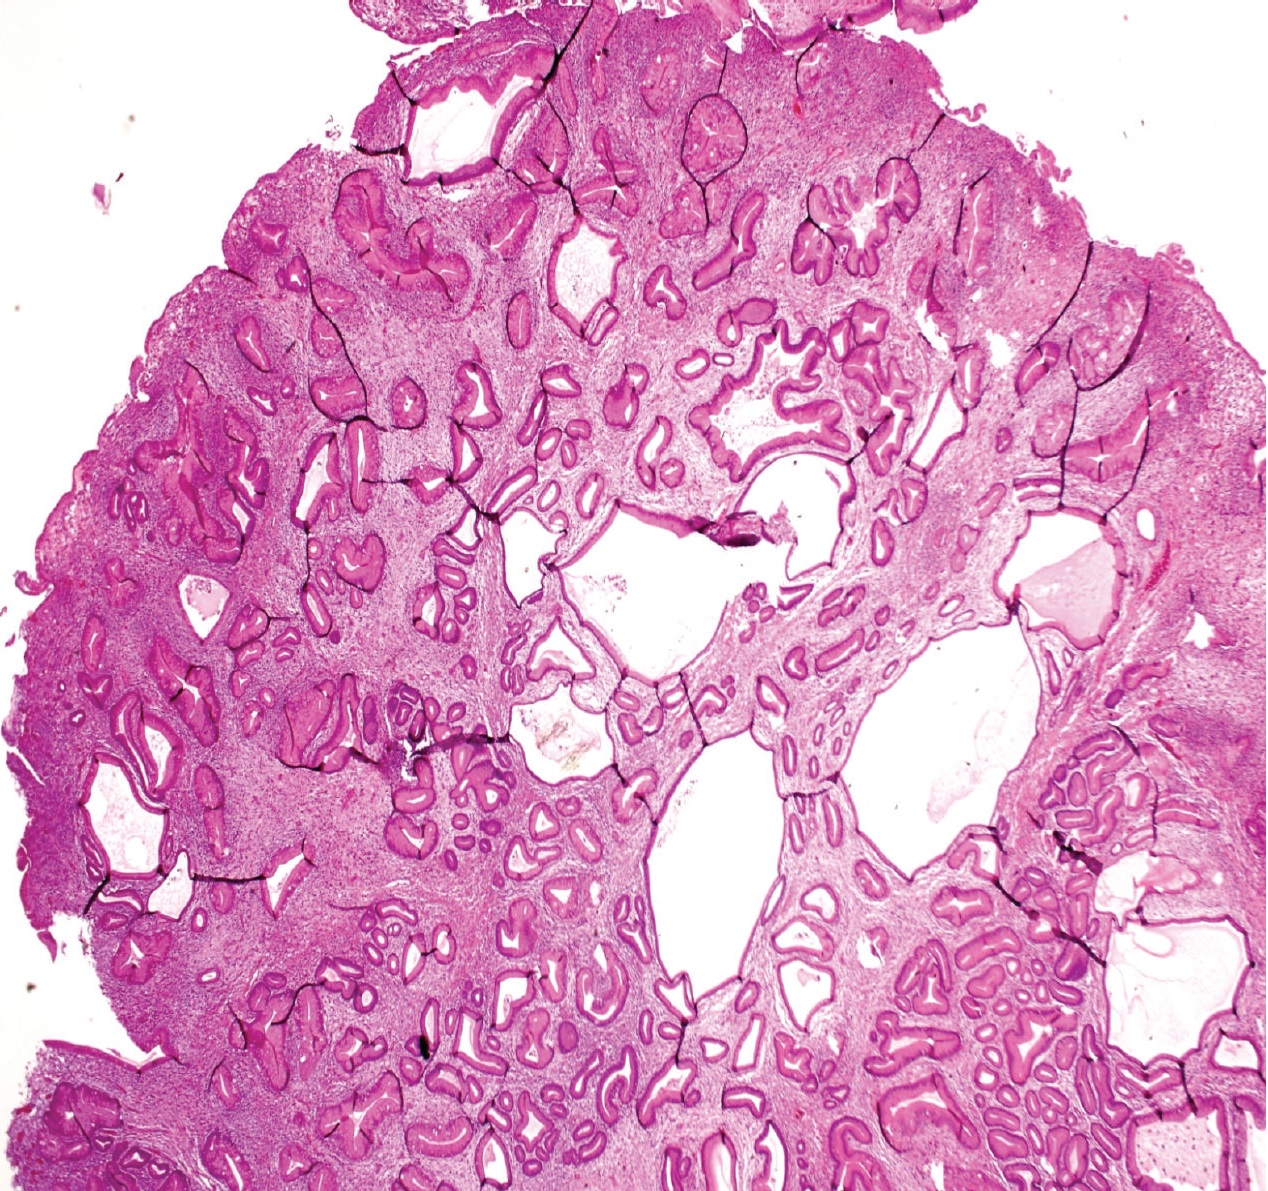

| 과형성 용종 | 대장 (별도로 명시되지 않는 한) | 톱니 모양의 분지되지 않은 샘 | 용종이 100개 이상인 경우 | ![]() | 톱니 용종증 증후군 |

| 과형성 용종 | 대장 (별도로 명시되지 않는 한) | 톱니 모양의 분지되지 않은 샘 | 용종이 100개 이상인 경우 | 톱니 용종증 증후군 | |